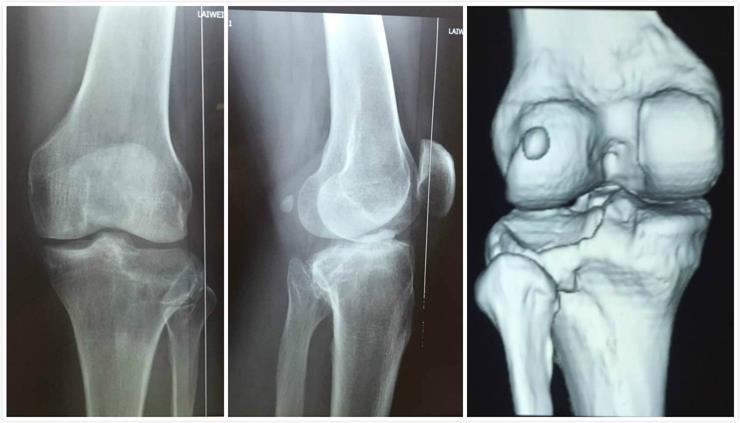

男性病人,43歲,左脛骨平臺后外側塌陷骨折。

術(shù)前影像學(xué)資料: